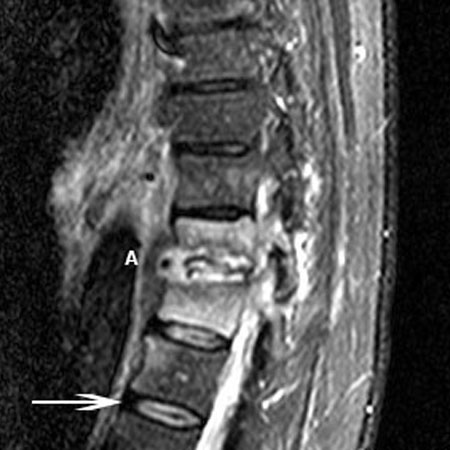

ოსტეომიელიტის მაგნიტურ-რეზონანსული კვლევა: T11-T12 დისკების სივრცე დაზიანებულია დისკის ანთებასთან ერთად (A). აღინიშნება ორივე მალის ძვლოვანი დაზიანება,რაზეც მიუთითებს მაღალი T2 სიგნალი მალების სხეულებზე. ისრით მითითებულია ნორმალური, დაუზიანებელი მალის დისკი

ექიმ Dr K. Singh საკუთრება; გამოყენებულია ნებართვით